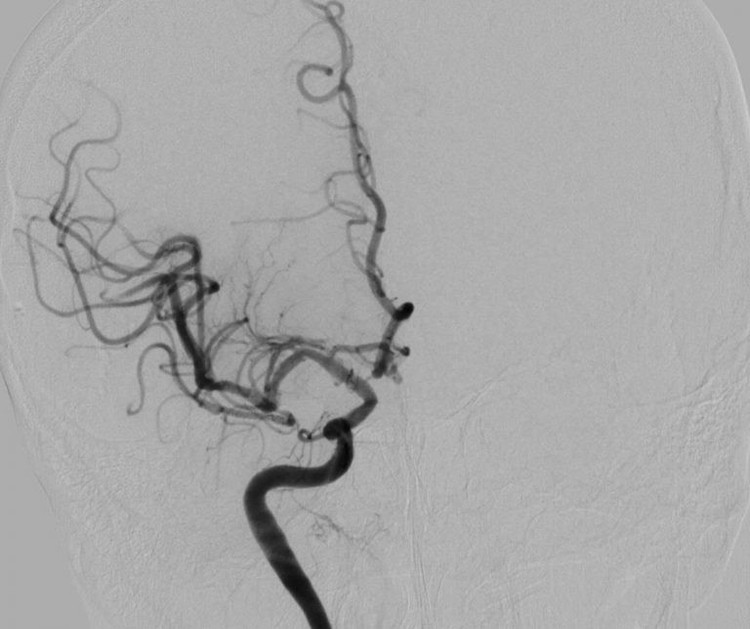

dot-quy-cao-4.jpg

Hình DSA tái thông hoàn toàn động mạch não giữa sau can thiệp của bệnh nhân đột quỵ - Ảnh BVCC

Ngay sau chẩn đoán và giải thích với sự đồng thuận của người nhà, bệnh nhân được chỉ định can thiệp mạch lấy huyết khối bằng dụng cụ.

Ca can thiệp đã diễn ra thành công dưới sự thực hiện của BS Lục Đình Phương, Khoa Sọ não cột sống 2, bác sĩ đã tiến hành tái thông động mạch não giữa và nong bóng đoạn hẹp động mạch cảnh trong bên phải cho bệnh nhân bằng phương pháp gây tê.

Sau can thiệp, các động mạch đã được tái thông, bệnh nhân hoàn toàn tỉnh táo, sức cơ cải thiện rõ rệt và được tiếp tục chuyển lên khoa Nội thần kinh để tiếp tục theo dõi và điều trị theo phác đồ nội khoa.